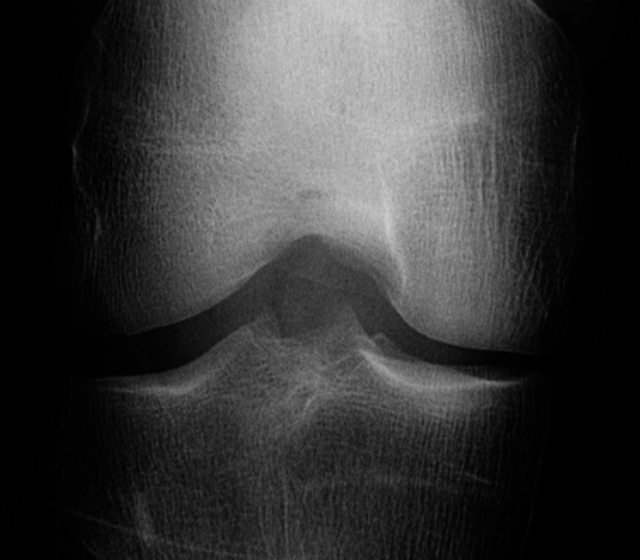

Knee OA develops gradually over years and progresses in stages. In general, the severity of knee OA is divided into five stages. The first stage (stage 0) corresponds to normal healthy knee and the final stage (stage 4) corresponds to the most severe condition (see Figure 2). The most commonly used systems for grading knee OA are the International Knee Documentation Committee (IKDC) system, the Ahlback system, and the Kellgren & Lawrence (KL) grading system. The other widely used non-radiographic knee OA assessment system is WOMAC666Western Ontario and McMaster Universities Osteoarthritis Index, which measures pain, stiffness, and functional limitation. The public datasets, the OAI and the MOST used in this work, are provided with the KL grades and they are used as the ground truth to classify the knee OA X-ray images.

Refer to caption

Figure 2: The Kellgren and Lawrence grading system to assess the severity of knee OA.

The KL grading scale was approved by the World Health Organisation as the reference standard for cross-sectional and longitudinal epidemiologic studies [7, 22, 24, 25]. The KL grading system is still considered the gold standard for initial assessment of knee osteoarthritis severity in radiographs [1, 5, 6, 7]. Figure 2 shows the KL grading system. The KL grading system categorizes knee OA severity into five grades (grade 0 to 4). The KL grading scheme for quantifying knee OA severity from X-ray images is defined as follows [1, 5]:

• Grade 0 : absence of radiographic features (cartilage loss or osteophytes) of OA.

• Grade 1 : doubtful joint space narrowing (JSN), osteophytes sprouting, bone marrow oedema (BME), and sub-chondral cyst.

• Grade 2 : visible osteophytes formation and reduction in joint space width on the antero-posterior weight-bearing radiograph with BME and sub-chondral cyst.

• Grade 3 : multiple osteophytes, definite JSN, sclerosis, possible bone deformity.

• Grade 4 : large osteophytes, marked JSN, severe sclerosis, and definite bone deformity.